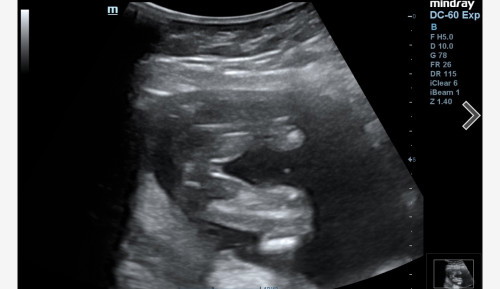

Girl or boy

Need confirmation, since gambar scan tak clear sangat. Tak berapa nampak burger sign. Comfirm ke girl?